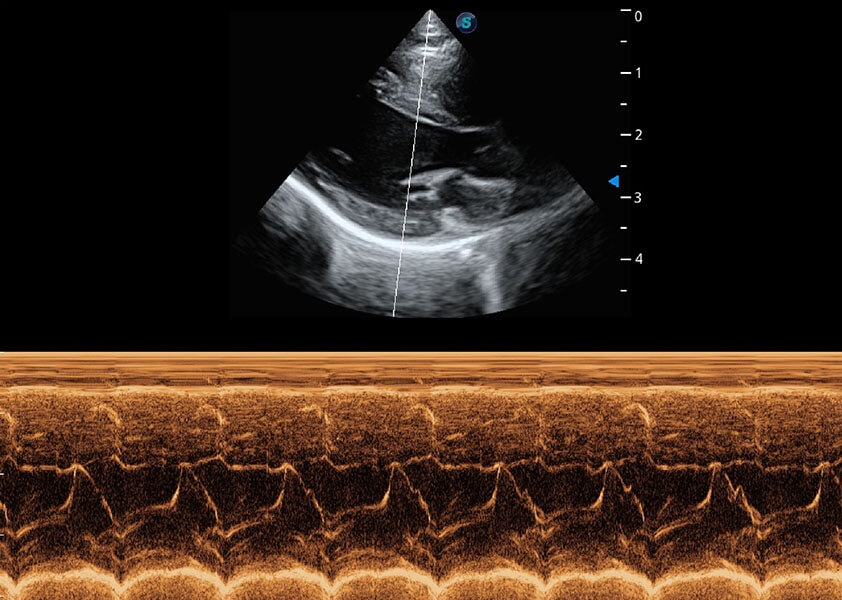

ProPet 60 作为一款高端台式动物超声设备,为动物医生的日常诊断提供了一系列贴合动物临床需求、解决临床实际问题的高级成像功能。凭借全系列高清探头,满足医生对腹部、心脏、生殖、浅表、肌骨等成像的所有需求,切实帮助您提升检查效率,提高诊断信心。

动物是人类最亲密的朋友和最值得信赖的伙伴。球速体育入口也一直致力于探索动物专用的超声影像解决方案。 全新推出的ProPet系列,是球速体育入口在动物超声影像智能化、专业化、精准化的一次跨越式革新。动物不能用言语来表述自己的不适,通过超声影像,ProPet系列搭建了动物医生与不同物种沟通的“桥梁”,为动物医生注入了“治愈之力”。